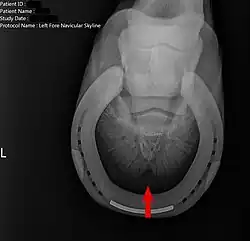

Hufrollenentzündung

Die Hufrollenentzündung entsteht meist durch Überlastung der Vorhand. Da sie den Knochen des Strahlbeins angreift, ist sie irreversibel und führt in der Regel zur Unreitbarkeit des betroffenen Pferdes.

Die Hufpflegeschule nach Straßer sieht eine häufige Ursache für eine Hufrollenentzündung in dem vernachlässigten Kürzen der Eckstreben sowie untergeschobenen Trachten, die zu einem Zwanghuf führen. Die Eckstreben werden hierdurch von unten in den Huf und gegen den Hufrollenmechanismus gedrückt, welches zur Lahmheit des Pferdes und zur Auslösung eines entzündlichen Prozesses an der Hufrolle führt. Der anatomisch korrekte Ausschnitt des Hufes, insbesondere das „Ausgraben“ der Eckstreben, sowie die Weitung des Zwanghufes durch Wiederherstellen des Hufmechanismus können nach Straßer zur Beseitigung der Lahmheit und der Hufrollenentzündung führen.